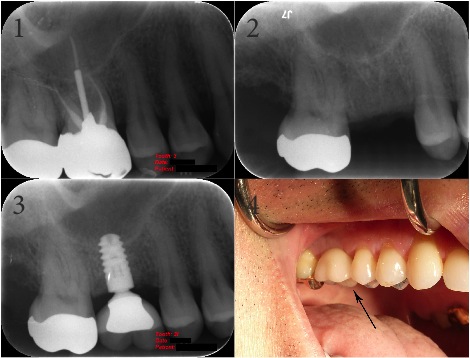

Endodontic & Implantology Associates Bone Grafting and Dental Implant Case Study: Case A

1. Fractured Tooth (Note: Fracture not visible in X-Ray)

2. Extraction of Fractured Tooth and Bone Graft

3. Final X-Ray with Implant

4. Final Implant